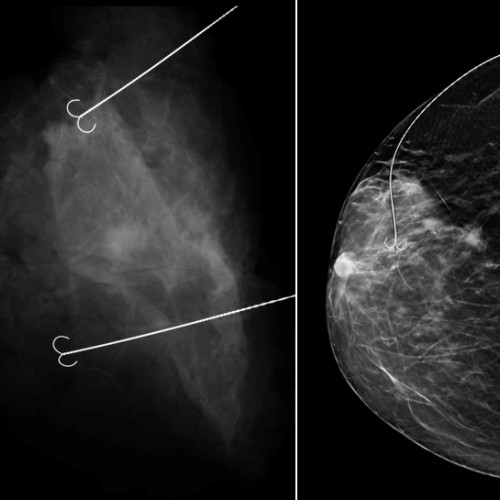

O echipă medicală multidisciplinară de la Spitalul Judetean Constanța a realizat o intervenție inovatoare pentru tratamentul patologiei mamare, reușind conservarea sânului pacientei. Potrivit site-ului ziarulamprenta.ro, în echipa au fost implicați specialiști precum Dr. Iulia Dogaru, medic chirurg, Dr. Cristina Bustiuc, medic primar ATI, și Dr. Alexandru Gavrila, medic primar radiologie și imagistică medicală, cu competență în senologie.